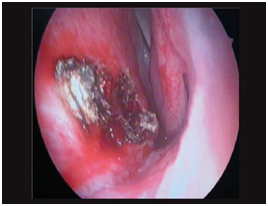

All the patients underwent diagnostic nasal endoscopy under local anaesthesia. Mass was attached to anterior part of the nasal septum in 23 patients (Figure 1) (Figure 2) and in 4 patients, it was arising around the choana (Figure 3).

Figure 2 Nasal endoscopic picture showing the mass attached to the nasal septum.